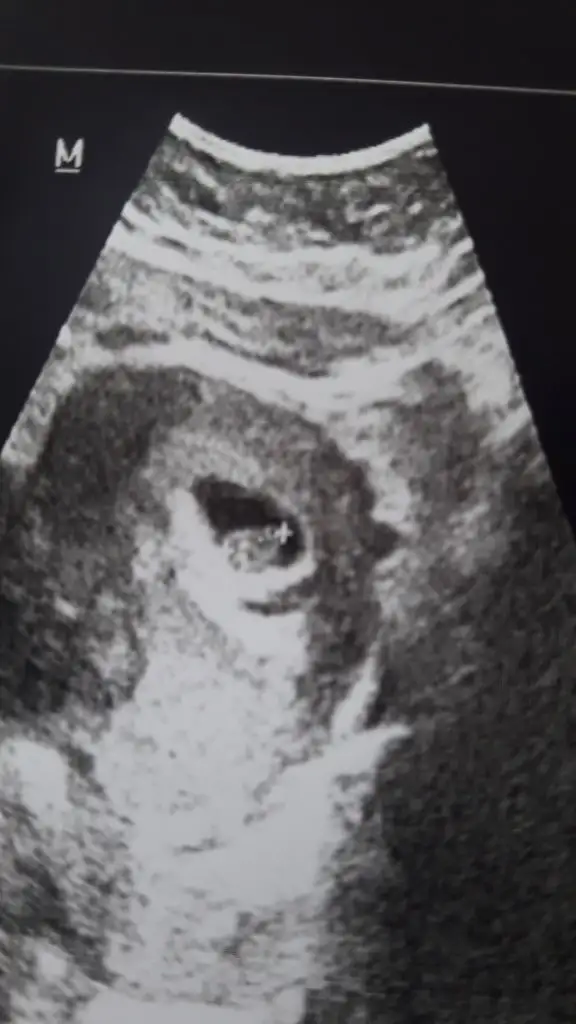

Karından ise Erkek buna göre en iyi 11 12 13 haftalar olmalı

Evet vajinelden ise erkek ama en iyi 11 12 13 haftalar olmalıVajinal bakildi canim farkediyor mu?

Evet karından 12. hafta tekrar rahatsız ederim o zaman çok teşekkür ederimKarından ise Erkek buna göre en iyi 11 12 13 haftalar olmalı